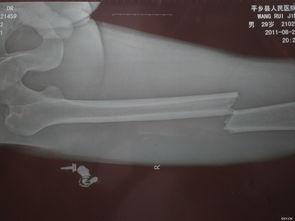

首先,让我们来认识一下髓内钉。髓内钉,顾名思义,就是一根插入骨髓腔内的金属钉子。它主要用于治疗长骨骨折,如股骨、胫骨等。髓内钉的优点在于,它能够有效地固定骨折部位,促进骨折愈合,同时减少手术创伤。

2. 手术过程:手术过程中,医生会在骨折部位切开皮肤,找到骨髓腔。使用特殊的工具将髓内钉插入骨髓腔,直至钉子的另一端露出骨折部位。

3. 固定骨折:在髓内钉插入骨髓腔后,医生会使用连接杆将钉子的两端连接起来,从而固定骨折部位。